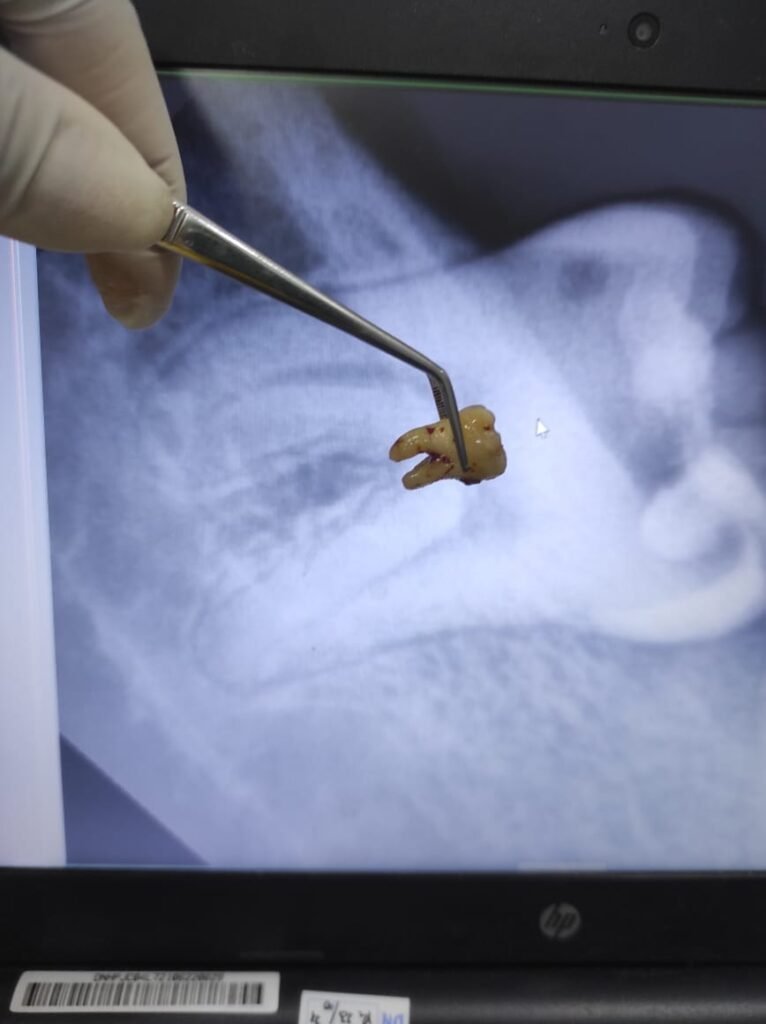

Pondok Gigi: Operasi Odontektomi Terpercaya Jakarta Selatan Apakah Anda sedang mencari tempat terbaik untuk operasi odontektomi di Jakarta Selatan? Klinik Pondok Gigi hadir sebagai solusi untuk Anda yang mengalami masalah gigi bungsu impaksi dan membutuhkan tindakan odontektomi profesional. Dengan layanan dari dokter spesialis bedah mulut berpengalaman, proses operasi di Pondok Gigi dilakukan sesuai standar medis […]

Operasi dan Konsultasi Operasi Gigi Bungsu Jakarta Selatan di Klinik Pondok Gigi Booking Konsultasi Apakah sobat Pondok Gigi sedang mengalami nyeri di bagian belakang mulut dan mencurigai Gigi Bungsu sebagai penyebabnya? Jangan khawatir, sobat Pondok Gigi tidak sendirian. Banyak orang di usia 17–30 tahun menghadapi masalah yang sama. Jika Sobat berada di wilayah Jakarta, […]